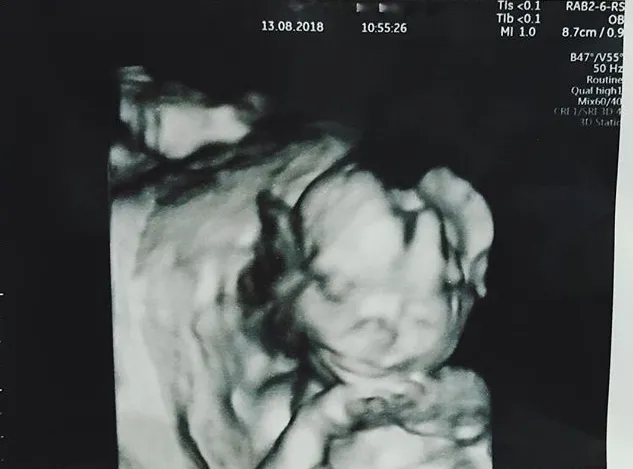

Setelah itu Tarra dan Gya pun melakukan USG dan bersyukur keadaan calon anak pertama mereka sehat. Namun mereka berdua belum tahu jenis kelamin sang jabang bayi karena menunggu hingga usia kehamilan masuk lima bulan.